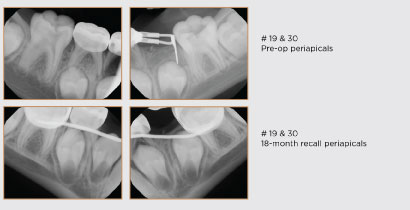

Figure 4 – Pulpotomy

A 9-year-old female presented for a comprehensive oral evaluation. The patient was asymptomatic at the time of evaluation and had no oral complaints. Upon evaluation, a stainless-steel crown was noted on tooth #30, and a periapical radiograph was ordered, taken, and interpreted. The radiograph showed an apparent open margin on the distal, with recurrent decay, and a widened periodontal ligament. The patient was anesthetized, and rubber dam isolation was placed. The crown was removed with a high-speed handpiece. After crown removal, the patient was symptomatic even though profound anesthesia was demonstrated. A temporary restorative material was placed, and the patient was rescheduled. At a subsequent visit, the patient obtained adequate anesthesia, and the tooth was found to be vital (asymptomatic irreversible pulpitis). A pulpotomy was performed with sodium hypochlorite and SmartMTA (Sprig) as hemostasis was obtained at the canal orifice. The tooth was restored with Ionolux (Voco GmbH). At a later recall, the tooth was subsequently restored with a stainless-steel crown (3M).